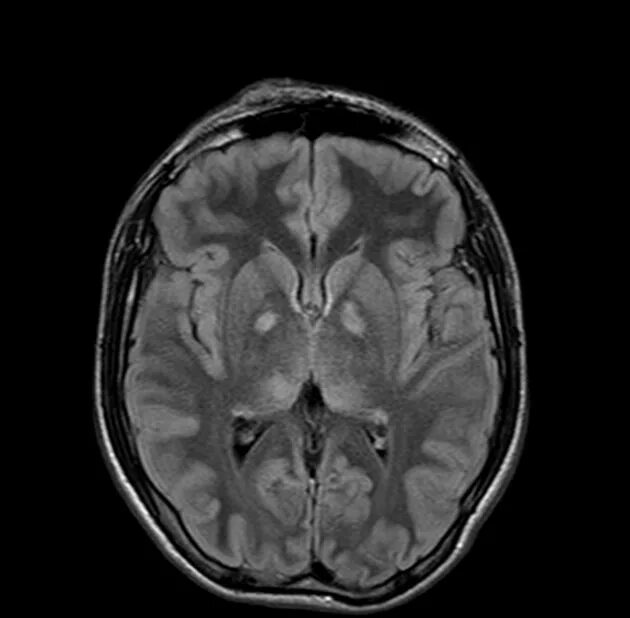

Нейрофиброматоз мрт